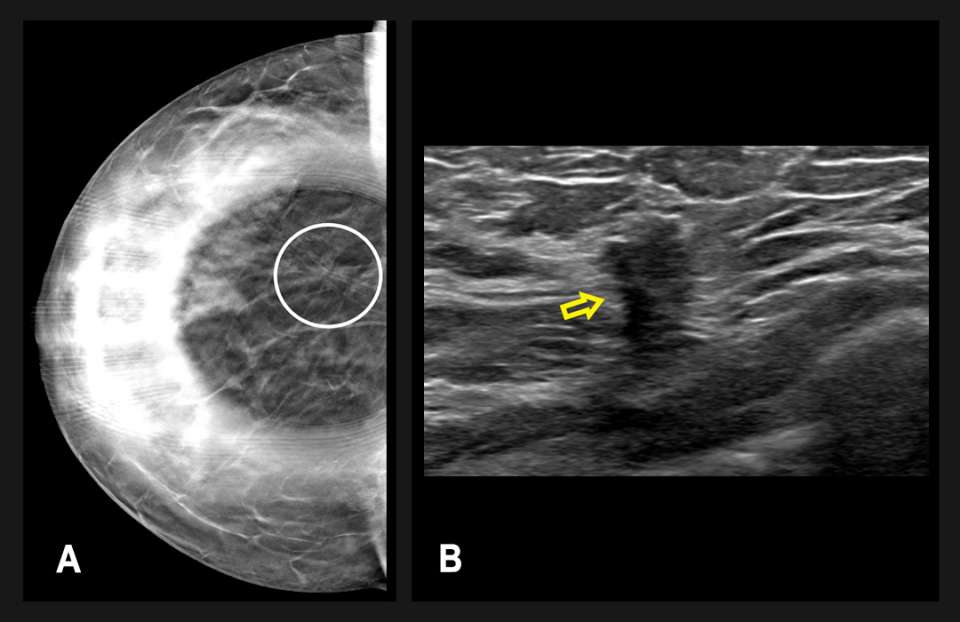

Diagnostic mammography followed one month thereafter and included spot compression views of the area of architectural distortion in the right breast (Figure 2A). Targeted breast ultrasonography showed a vague hypoechoic area measuring up to 11 mm, which correlated with the mammographic findings (Figure 2B). The finding was categorized as BI-RADS 4B, and an ultrasound-guided biopsy was recommended.

Figure 2: (A) Diagnostic right breast mammography and (B) right breast ultrasound of the same patient. There is a persistent architectural distortion on spot compression mammography in the lower outer quadrant, seen both on CC (circled) and mediolateral (not pictured) views. Targeted ultrasonography showed a vague hypoechoic area (arrow) measuring 11 x 7 x 6 mm at 7 o’clock, 9 cm from the nipple, correlating with the mammographic finding. The finding was classified as a BI-RADS Category 4B and ultrasound-guided biopsy was recommended.